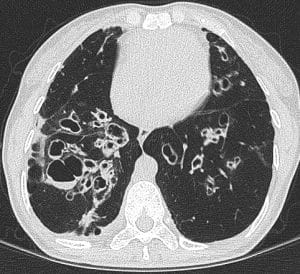

Bronchiectasis is a lung disease characterised by the permanent widening of the bronchial tubes, causing them to lose their normal shape and ability to clear mucus.

Clinically it is associated with cough, production of phlegm (mucus) and recurrent chest infection.

Bronchiectasis is a complex disease with a multifactorial pathogenesis that involves damage to the airways and an ongoing cycle of infection and inflammation.